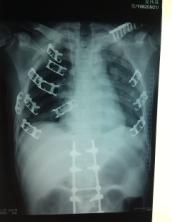

专业技术水平创伤骨科:开展复杂关节内骨折、复杂骨盆骨折、脊柱骨折、四肢骨折、锁骨、肩胛骨、各类陈旧性骨折、骨缺损、胸廓成型术治疗;开展严重创伤皮肤软组织缺损的带血管蒂皮瓣专业修复治疗。

我科通过长期为云锡矿区服务,在创伤急救方面累积了丰富的实践经验,成功抢救了一大批多发伤的危重病人,并得到了社会各界人士的一致好评。如:创伤性失血性休克,全身复合伤等。开展的手术有:四肢骨干骨折、复杂关机内骨折、脱位的手术治疗;脊椎骨折脱位的开放复位内固定术,复杂骨盆、髋臼骨折手术治疗;颈椎、腰椎间盘突出髓核摘除减压手术治疗;人工全髋关节置换,人工膝关节置换等手术治疗。